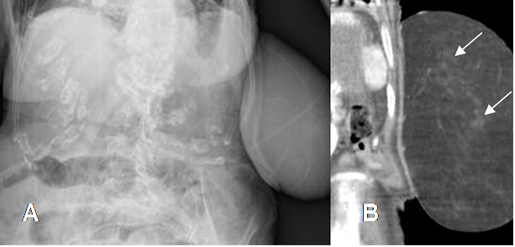

Fig 157 A. Lipoma.

A: Rx AP y B. RM coronal en STIR. Prominencia de tos tejidos blandos hacia la parte lateral del antebrazo, con imagen ovalada y con densidad de grasa, similar al tejido celular subcutáneo, que corresponde a lipoma.